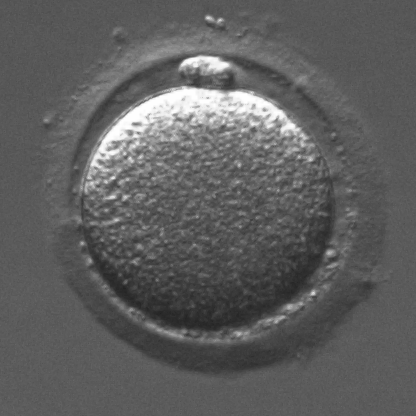

Infertility is becoming an issue for an increasing number of couples. The most common solution, in vitro fertilization, requires embryologists to carefully examine light microscopy images of human oocytes to determine their developmental potential. We propose an automatic system to improve the speed, repeatability, and accuracy of this process. We first localize individual oocytes and identify their principal components using CNN (U-Net) segmentation. Next, we calculate several descriptors based on geometry and texture. The final step is an SVM classifier. Both the segmentation and classification training is based on expert annotations. The presented approach leads to a classification accuracy of 70%.